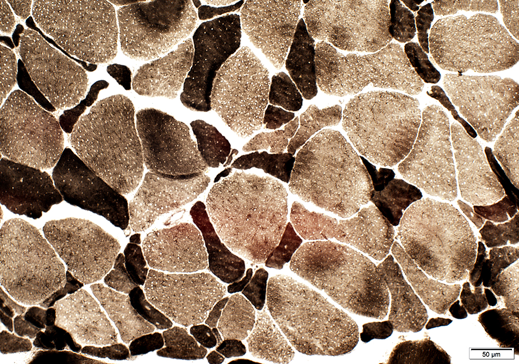

Weakness, difficulty relaxing hand

Myotonic Dystrophy – on the left shows multiple internal nuclei characteristic of myotonic dystrophy.

This disease features more internal nuclei than any other muscle disorder.

The right longitudinal section shows that the interal nuclei within the muscle fibers also tend to line up. Note the increase in connective tissue.

Myotonic dystrophy results from a triplet repeat expansion of the myotonin gene on chromosome 19; more severe anticipation occurs with maternal inheritance